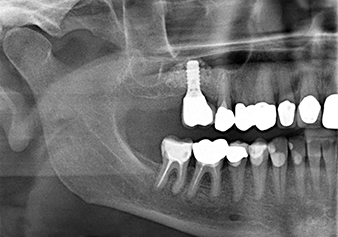

Una paziente di 49 anni, non fumatrice e con un'anamnesi priva di elementi rilevanti, è stata indirizzata al nostro studio di chirurgia orale per l'estrazione chirurgica del dente 16 ed il successivo impianto. Dopo l'estrazione, la paziente ha accusato dei lievi dolori causati dalla sinusite, motivo per cui abbiamo inizialmente aspettato sei mesi prima di procedere con l'intervento. L'altezza ossea residua in corrispondenza della posizione dell'impianto misurava 3-4 mm (Fig. 1 e 2).

Fig.1: Valutazione preoperatoria: la cresta alveolare è guarita bene, compresa la gengiva sufficientemente ampia e cheratinizzata.

Fig.2: il DVT mostra le corrette dimensioni in ogni vista assiale (sinistra), laterale (in alto) e trasversale (destra). La membrana del seno mascellare è ancora leggermente ispessita.